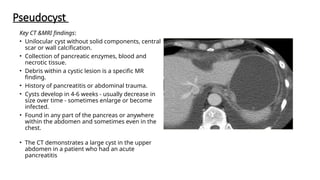

Key CT &MRI findings:

• Unilocular cyst without solid components, central

scar or wall calcification.

• Collection of pancreatic enzymes, blood and

necrotic tissue.

• Debris within a cystic lesion is a specific MR

finding.

• History of pancreatitis or abdominal trauma.

• Cysts develop in 4-6 weeks - usually decrease in

size over time - sometimes enlarge or become

infected.

• Found in any part of the pancreas or anywhere

within the abdomen and sometimes even in the

chest.

• The CT demonstrates a large cyst in the upper

abdomen in a patient who had an acute

pancreatitis